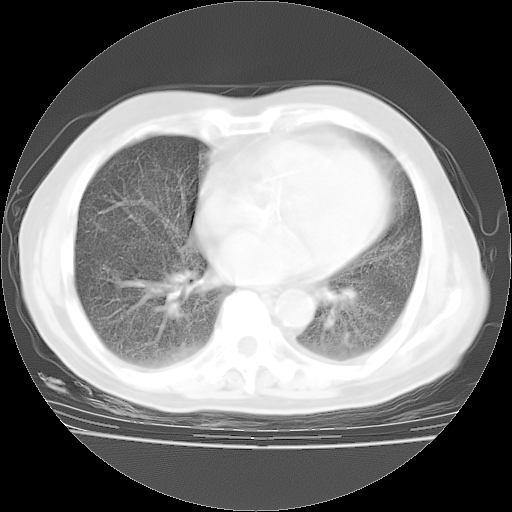

4月14日肺部CT